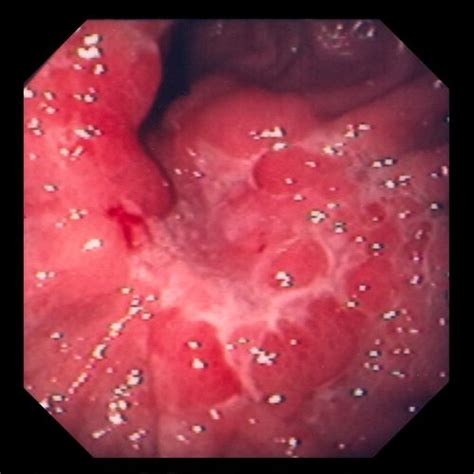

How Do U Know You Have Stomach Cancer / Cancer Archives - Today's Parent : Also called gastric cancer, the disease usually grows slowly over many years.. Stomach cancer (also known as gastric cancer) is usually found when a person goes to the doctor because of signs or symptoms they are having. People no longer feel hungry and ultimately start losing weight without trying, says dr. Early stomach cancer can have very mild symptoms. The color of blood in the stool often provides important clues as to the origin of bleeding. Your symptoms are unlikely to be cancer but it is important to get them checked by a doctor.

Blood in the stool can be a symptom of stomach cancer but can occur with other noncancerous conditions as well. They are similar to indigestion symptoms. This can also happen if you: This is the subject of ongoing research. Some common signs of metastatic cancer include: Patients report vomiting blood, or passing blood. Bright red blood in the stool, also known as hematochezia, is generally not a sign of stomach cancer. Stomach cancer, also known as gastric cancer, can affect any part of the stomach. If stomach cancer is suspected, exams and tests will be needed to find out for sure. There are many known risk factors for stomach cancer (also called gastric cancer), but often it's not clear exactly how these factors might affect how cells in the stomach become cancer cells. Gas in the stomach often results from swallowing too much air while eating or drinking. Symptoms of early stomach cancer can be similar to the symptoms of other conditions, such as stomach ulcers. People over 40 years old are prone to stomach cancer.

When stomach cancer does cause signs and symptoms, they can include: Stomach cancer can be genetic. Stomach cancer develops when cells in the lining of the stomach grow and divide abnormally. The cancer has not spread to lymph nodes or other tissues or organs, but has grown through the main muscle layer of the stomach wall into the subserosa (the thin layer between the main muscle layer of the stomach and the outside membrane of the stomach, called the serosa). Gas in the stomach often results from swallowing too much air while eating or drinking. If you have relatives that have had stomach cancer, then you could be at risk, as signs of stomach cancer are generally unnoticeable until the disease is at a developed stage. Bright red blood in the stool, also known as hematochezia, is generally not a sign of stomach cancer. They are similar to indigestion symptoms. When symptoms do occur, they may be vague and can include those listed below. People over 40 years old are prone to stomach cancer. You should see your doctor if you have unexplained weight loss or you have symptoms that are unusual for you or that won't go away. Tumours can begin anywhere in the stomach but most begin in the glandular tissue on the stomach's inner surface. Sometimes there are no signs or symptoms of stomach cancer or duodenal or gastric ulcers, and when they do occur, they may include nausea and loss of appetite with no clear cause.